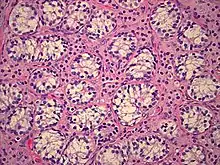

AIS results when the function of the androgen receptor (AR) is impaired. The AR protein (pictured) mediates the effects of androgens in the human body. | |